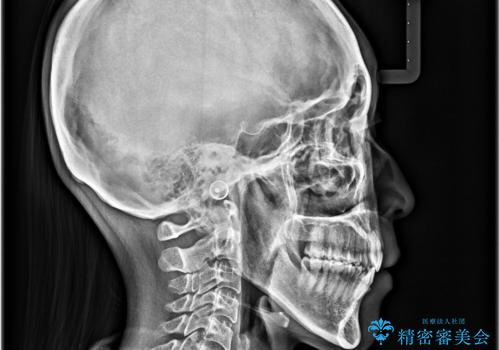

舌の突出癖を改善するためのトレーニングをしっかりと行っていただいたことで、比較的スムーズに治療を進めることができました。

口元の突出感もしっかりと改善することができました。